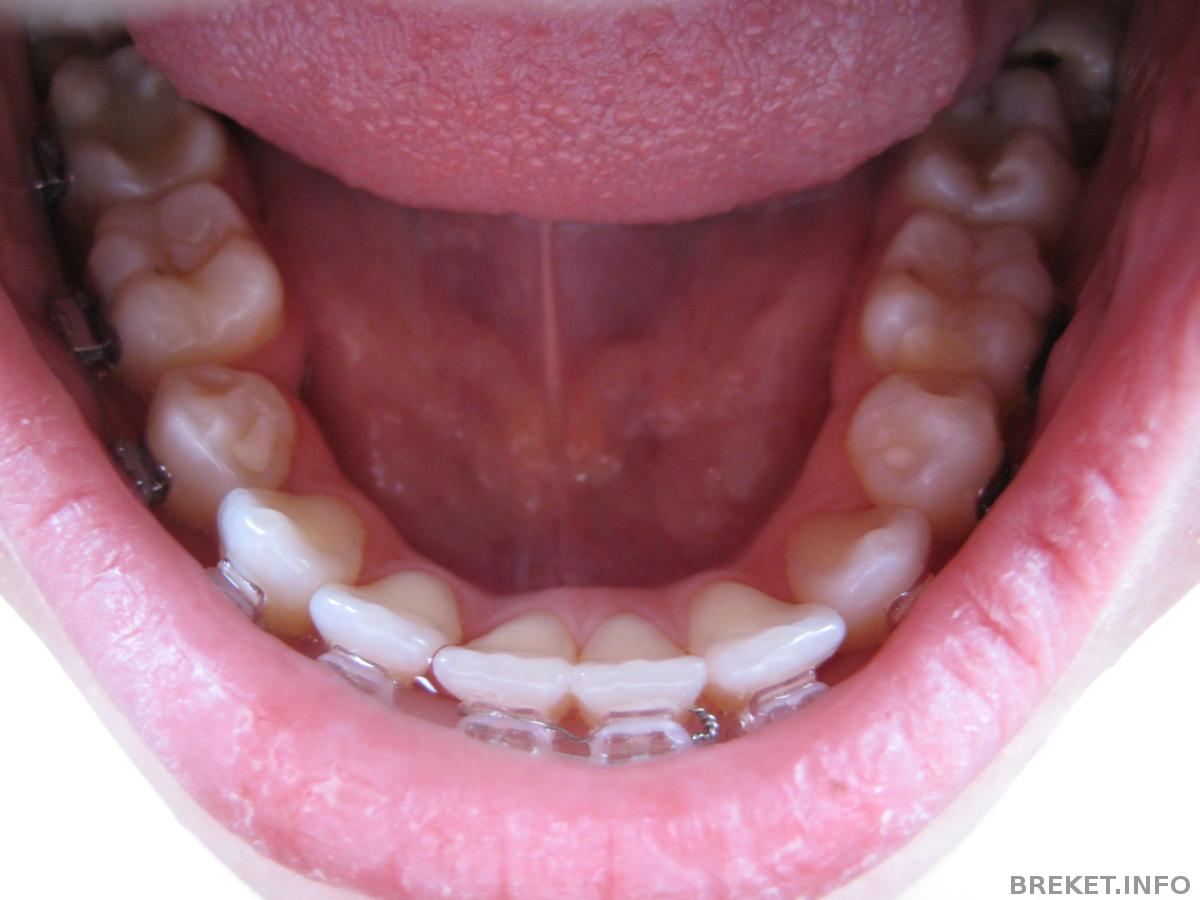

Между 1-ми на НЧ была щель, завязали это дело проволочкой, щель моментально испарилась, но появилась щель между 1-ей и 2-ой((( Буду снова "дырявая ходить" ![]()

Про ретейнеры: на НЧ обязательно надо несъемник и съемный, на ВЧ до конца не поняла. Один надо обязательно, вроде бы несъемник, но я для подстраховки, наверное, закажу оба. Еще про НЧ она сказала, что там, где удаляли зубки, чтобы не разъехалось (а щель появилась с проблемной стороны снова после снятия чейна((((( печальбеда, а не промежуток), тоже как-то закрепит. Вроде бы капнет этим составом. Вобщем гадать не буду, на снятии все будет понятно.